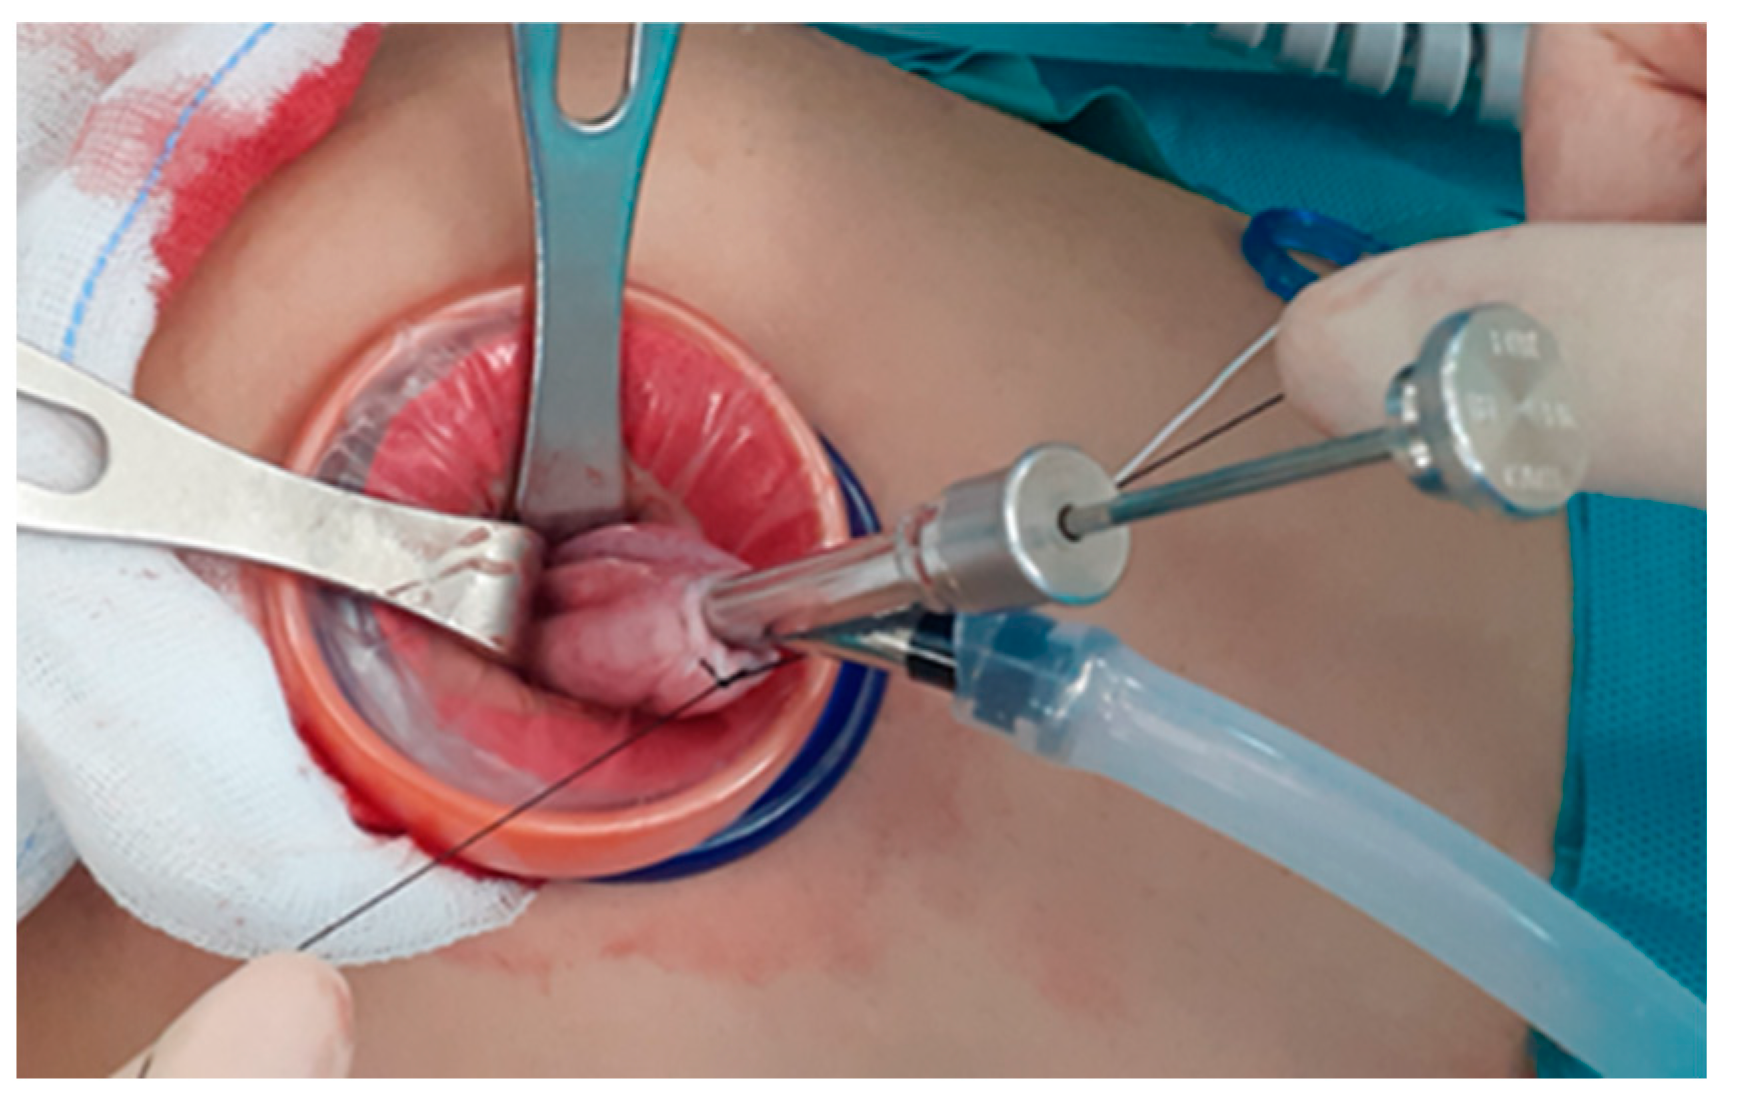

Figure 2. In cases of very large ovarian masses that could not be placed even in an extra-large endo-bag, the size of the mass was decreased using a technique of placing a purse-string suture on the surface of the ovary and inserting the OSCHNER trocar into the mass through the circle of the purse-string sutures to drain the cystic contents. When there is nothing left to be drained, the suture is tied while simultaneously drawing the OSCHNER trocar out of the cyst to seal the trocar insertion site to prevent spillage of the cystic contents.